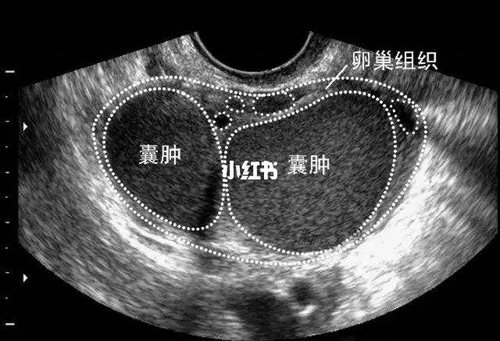

身体内的很多部位都会出现囊肿,比如说肝囊肿、胃囊肿等。这些囊肿不易发现,通常会在体检时检查出来,检查结果还会出现囊肿囊壁厚这样的描述,患者往往会对这样的描述感到担心。那么,囊肿囊壁厚是什么意思呢?

囊肿囊壁厚是说明囊肿增厚3-5厘米。囊肿囊壁厚并不说明病情有特殊性,也不能说明囊肿是良性还是恶性的,所以发现自己的这种现象之后患者不要太过于担心。不过如果囊肿超过了5厘米,那最好不要耽误,最好尽早寻找医生的帮助,及时进行规范的治疗。

囊肿囊壁厚对病情的性质以及严重程度无关,我们不要太在意。患者最应该关注的是囊肿的大小以及生长速度,并且根据具体的病情结合医生的建议选择合适治疗方案。同时患者还要注意生活中的卫生。平时定期的进行复查,以尽量避免病情的复发。